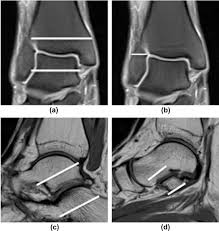

Pitfalls In Mri Of The Developing Pediatric Ankle Radiographics

Pitfalls In Mri Of The Developing Pediatric Ankle Radiographics from pubs.rsna.org

Mri scans are sensitive to motion and any motion may obscure information the radiologist uses to make a formal report. You'll be given earplugs or headphones to wear. We are taking hundreds, sometimes thousands of images and it takes the machine several minutes to acquire these slices. You can expect your child to be in the mri scanner for about 60 minutes if the doctor orders an mri with contrast. There are no known harmful effects from the strong magnetic field used for an mri. How long does the mri take? An ultrasound can show the tendon in high detail as can an mri (3). Silverman to provide a list of five reasons why someone would need an mri on their foot or ankle.